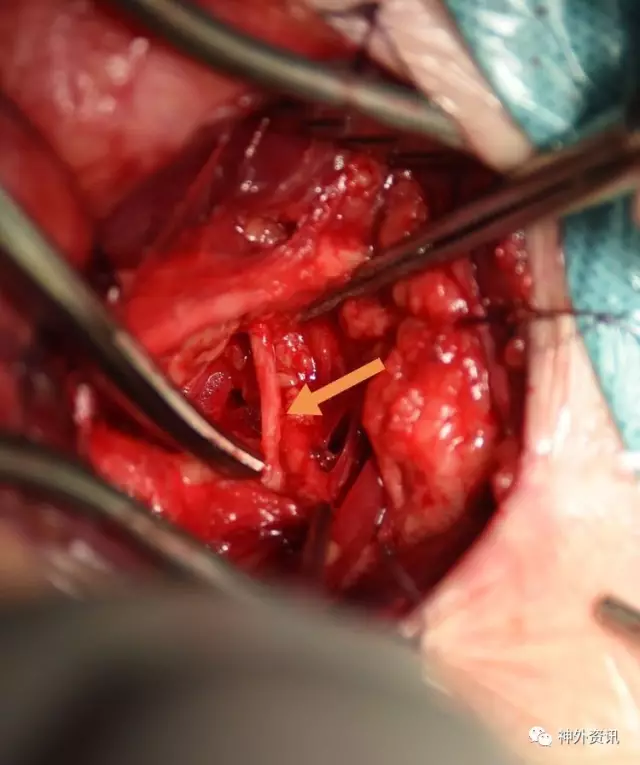

赵鹏博士在做手术显露,病人服着单抗,这个层次很明晰,手术视野基本是无血手术,这样的术野你能看到每一条血管和神经,术中副损伤和意外情况会降到最低

从胸锁乳突肌内外侧头之间纵行分开肌束,观察内部结构,这个术野依然是那么清晰

在肌肉下方我们发现了横向外下的胸导管,黄箭头所示

充分游离、显露ⅤA起始段,锁骨下动脉向内外显露各约1.5cm,于血管下留置橡皮条,以方便术中阻断

标记VA内置支架段内膜剥离直切口,阻断锁骨下动脉远近端,马上可以切除支架了

切开外中膜,先切开支架远端管腔,手术的关键是摘除支架,而远端血管通畅我们的手术会更有把握,刀尖切到之处有颅内反向血流溢出

切开外膜你看到了M,亮晶晶的金属支架嵌入增生内膜

支架马上就摘除了,成功在望

这是剥离支架后的外中膜

显微镜下7-0缝线缝合切口,松开阻断夹,VA管腔充盈好,无活动渗血,手术很顺利

这是切下的标本,切开后见支架被增生内膜包裹,内腔消失